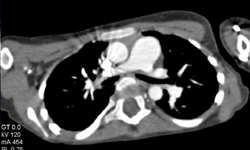

Aortic Dissection